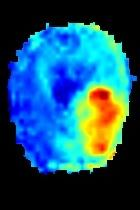

Current unsupervised anomaly localization approaches rely on generative models to learn the distribution of normal images, which is later used to identify potential anomalous regions derived from errors on the reconstructed images. However, a main limitation of nearly all prior literature is the need of employing anomalous images to set a class-specific threshold to locate the anomalies. This limits their usability in realistic scenarios, where only normal data is typically accessible. Despite this major drawback, only a handful of works have addressed this limitation, by integrating supervision on attention maps during training. In this work, we propose a novel formulation that does not require accessing images with abnormalities to define the threshold. Furthermore, and in contrast to very recent work, the proposed constraint is formulated in a more principled manner, leveraging well-known knowledge in constrained optimization. In particular, the equality constraint on the attention maps in prior work is replaced by an inequality constraint, which allows more flexibility. In addition, to address the limitations of penalty-based functions we employ an extension of the popular log-barrier methods to handle the constraint. Comprehensive experiments on the popular BRATS'19 dataset demonstrate that the proposed approach substantially outperforms relevant literature, establishing new state-of-the-art results for unsupervised lesion segmentation.